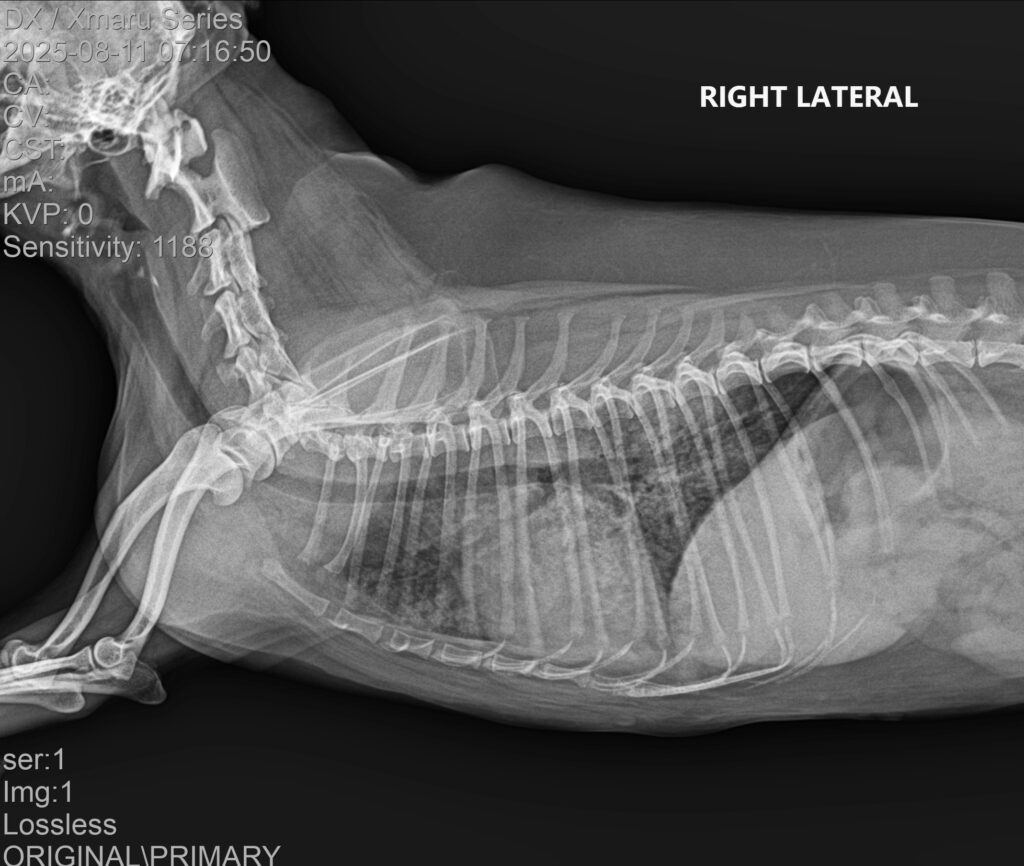

3. 흉부 방사선(X-ray) 검사

흉부 방사선 검사에서는 폐야 전반에 걸친 광범위한 침윤 소견이 관찰되었습니다.

내원 당시 흉부 방사선 사진/ 출처: 강서YD동물의료센터